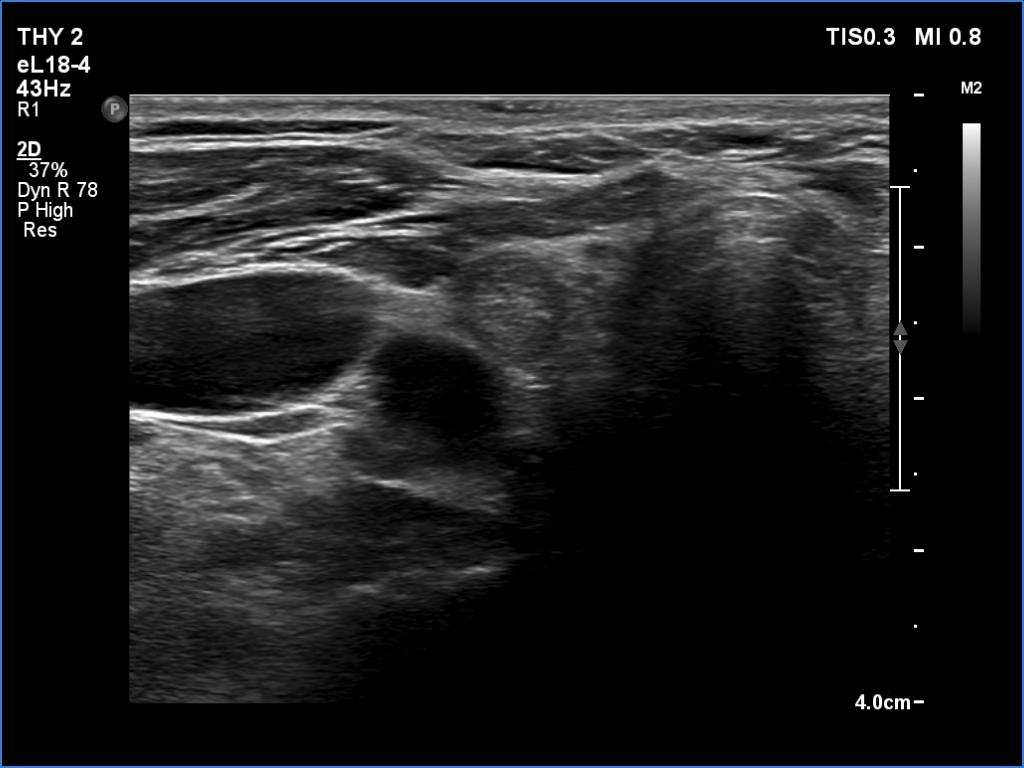

Ultrasonography. Both lobes had discrete lesions. The volume of the lobes were approximately one-tenth and one-third of a normal lobe, right and left lobe, respectively. The possibility of a true nodule should be considered in the event of the lesions in the left lobe.